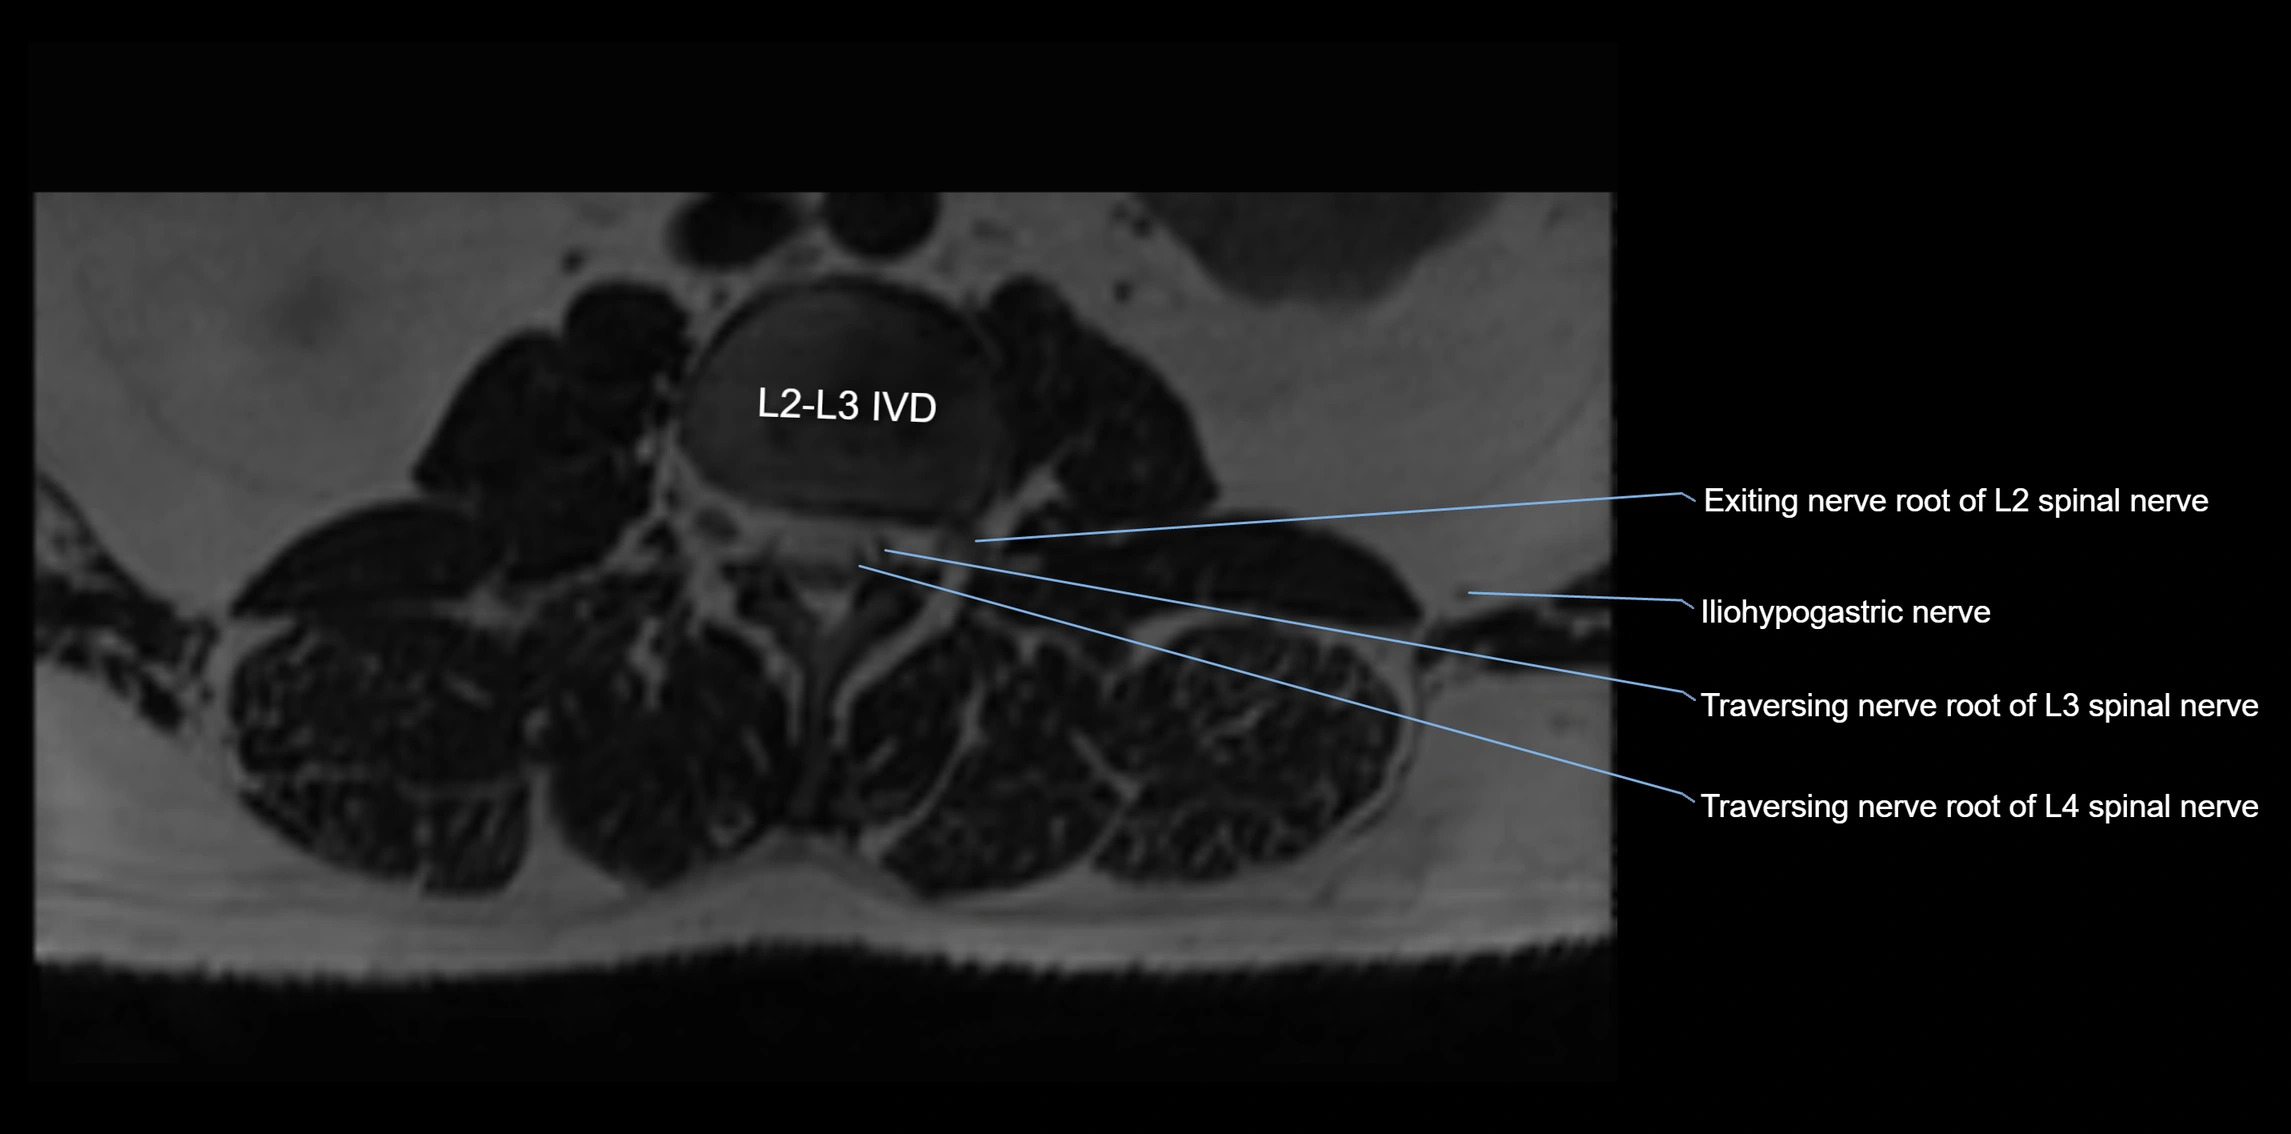

MRI image

image